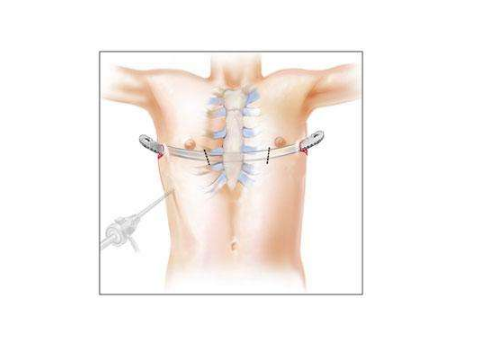

漏斗胸圖片

漏斗胸的

A:小兒漏斗胸的治療主要是以手術治療方式為主,臨床上可分為傳統手術方法以及微創矯形手術。傳統的手術包括胸骨翻轉術以及胸肋抬舉術兩種, 但是對於傳統手術,對孩子的創傷比較大。所以臨床上,目前採用微創漏斗胸矯形手術的方式比較多,是將塑形好的合金鋼板……